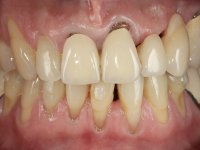

66-year-old male patient, non-smoker. It featured a 5-member metal-ceramic bridge with extreme mobility. Teeth 11 and 21 had infiltrated cervical margins. Both arches showed root exposure with signs of cervical abrasion. Composite resin “slots” were visible on the buccal surfaces of some mandibular teeth compatible with an orthodontic treatment with aligners that the patient was undergoing. After the imaging examination, it was found that the bridge's distal support, tooth 24, was irretrievably lost. The mesial pillars 11 and 21 had endodontic treatment and intraradicular posts. Teeth 25 and 26 also had endodontic treatment and extensive restorations in composite resin. In the lower jaw, two bridges were visible. In the third quadrant a 4-element bridge supported on tooth 35 and on 2 implants placed in the location of teeth 36 and 37. In the fourth quadrant a 3-element bridge supported on tooth 45 and an implant placed in the location of tooth 46. The patient presented a thick gingival phenotype and very good oral hygiene.